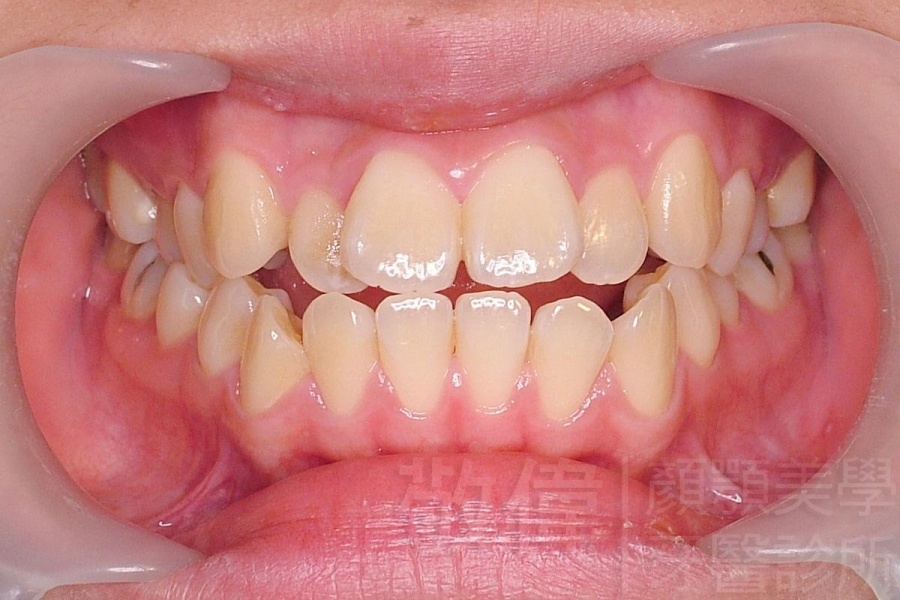

齒顏矯正/戽斗、亂牙、爛牙,變身 免植牙的健牙美女

變臉矯正,原來戽斗妹跟大歪臉變成自信正妹

經由本院3D數影X光影像儀分析、與3D齒顎顏矯正技術,再配合口腔顎面正顎專科醫師施以正顎手術治療,雙方共同合作,使患者臉部外觀有很好的改善,大歪變小歪,產生了天南地北的大改變,她的人生也整個變得不一樣。

因為矯正與正顎手術的配合,使「戽斗妹」變成了「陽光正妹」,完全的改變了她的人生,在面對各種場合、與人交際都散發出自信微笑。所以,奉勸家長,如果小朋友有臉顎畸型的問題,應該考慮配合做這種簡單、安全、有效的正顎手術。